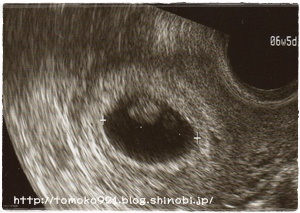

このエコー写真を撮った丸2週間後の9月1日にもう一度病院へ行きました。

090901.jpg

赤ちゃん発見!!

袋の上の方にいてはりました(*´∀`*)

心臓も動いているのが分かりました~!!